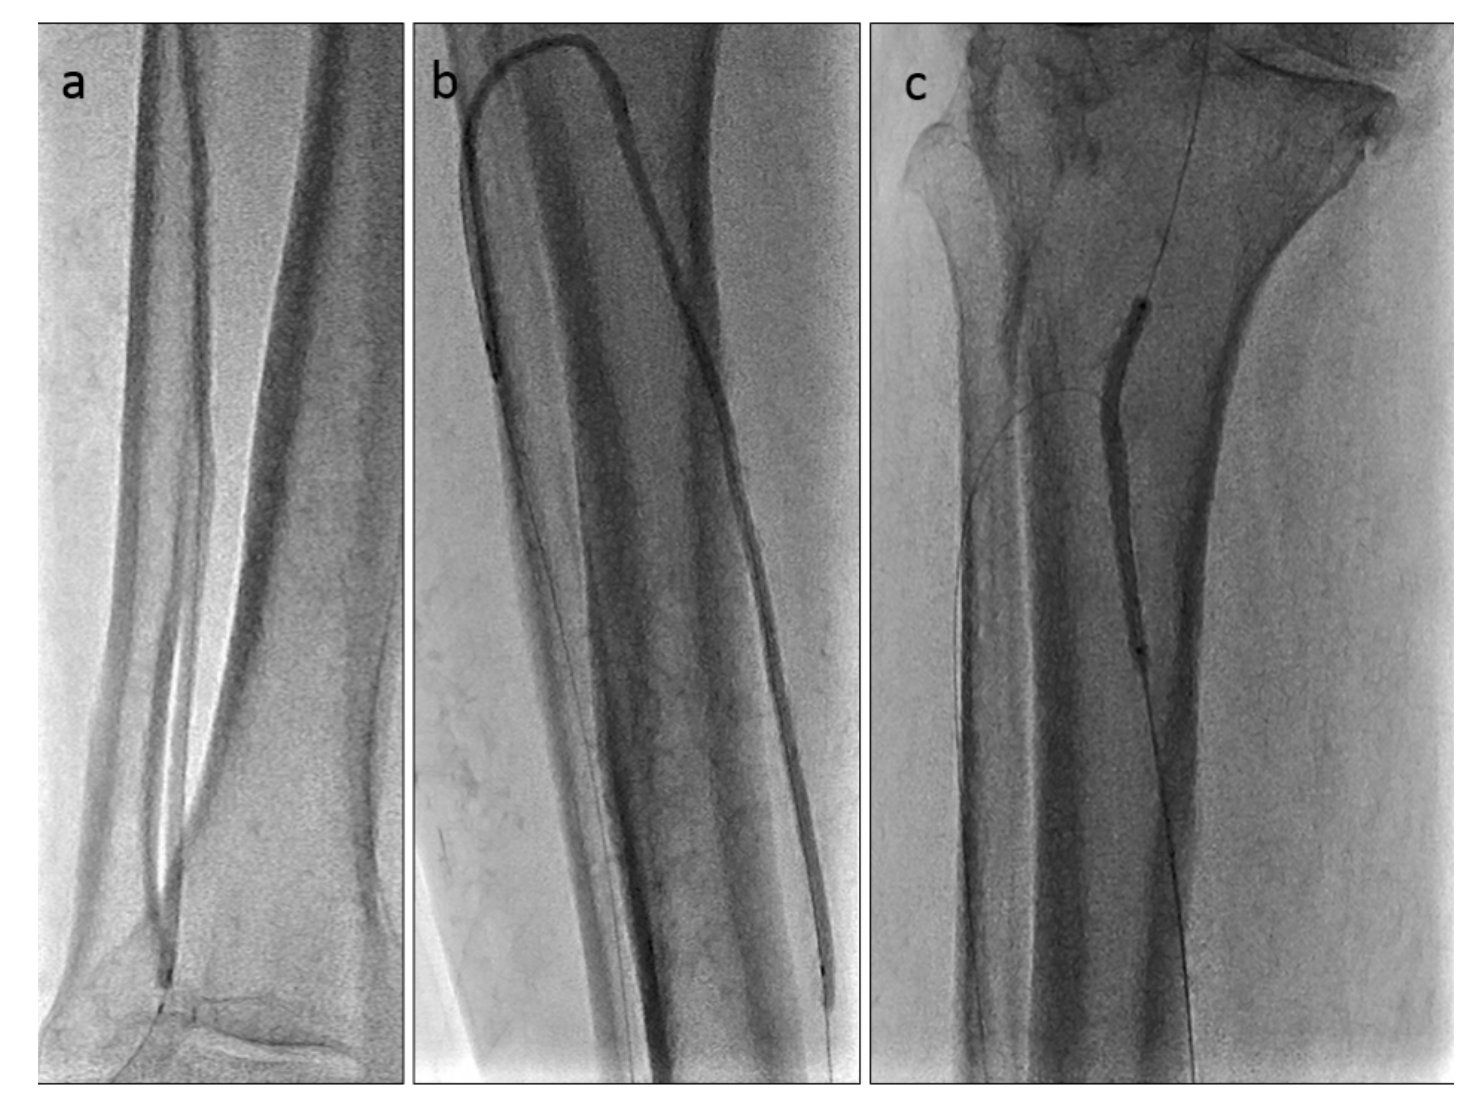

Anticipating a high risk of complications related to transfemoral access, we decided to proceed with a TAMI approach utilizing transradial guidance. A 4 to 5 French (Fr) Glidesheath Slender sheath (Terumo) was inserted in the right radial artery for visualization of the proximal vessels. We placed a 2.9 Fr Cook pedal sheath (Cook Medical) in the AT and advanced an .018-inch CXI support catheter (Cook Medical) over an .018-inch Command ST wire (Abbott Vascular). The CXI catheter and wire were advanced through the course of the ATA intraluminally, except for the ostium of the ATA, where the wire entered a subintimal space. Thereafter, we gained access in the right PT with a 4 to 5 Fr Glidesheath Slender sheath to serve as an antegrade access to cross the ATA CTO (Figure 2). An .018-inch CXI support catheter was telescoped within a 4 Fr Berenstein catheter (Boston Scientific) with an .018-inch Command wire advanced into the proximal AT (Figure 3). The antegrade equipment was advanced into the distal AT. The retrograde CXI catheter was pulled back in the distal AT, where the antegrade wire was inserted for externalization. Subsequently, the antegrade CXI catheter was externalized through the retrograde 2.9 Fr sheath placed in the distal AT (Figure 4). The .018-inch Command wire was exchanged for an .014-inch ViperWire (Cardiovascular Systems, Inc. [CSI]) guidewire to perform atherectomy using a 1.5 mm classic crown Diamondback 360 catheter (CSI) in the PT, TPT, and AT (Figure 5). Thereafter, based on extravascular ultrasound (EVUS) measurements, we performed balloon angioplasty of the proximal DP, AT, and PT with a 3.5 x 300 mm Ultraverse balloon (BD), and TPT with a 4.0- x 60-mm Lutonix drug-coated balloon (BD) with an excellent result (Figure 6).